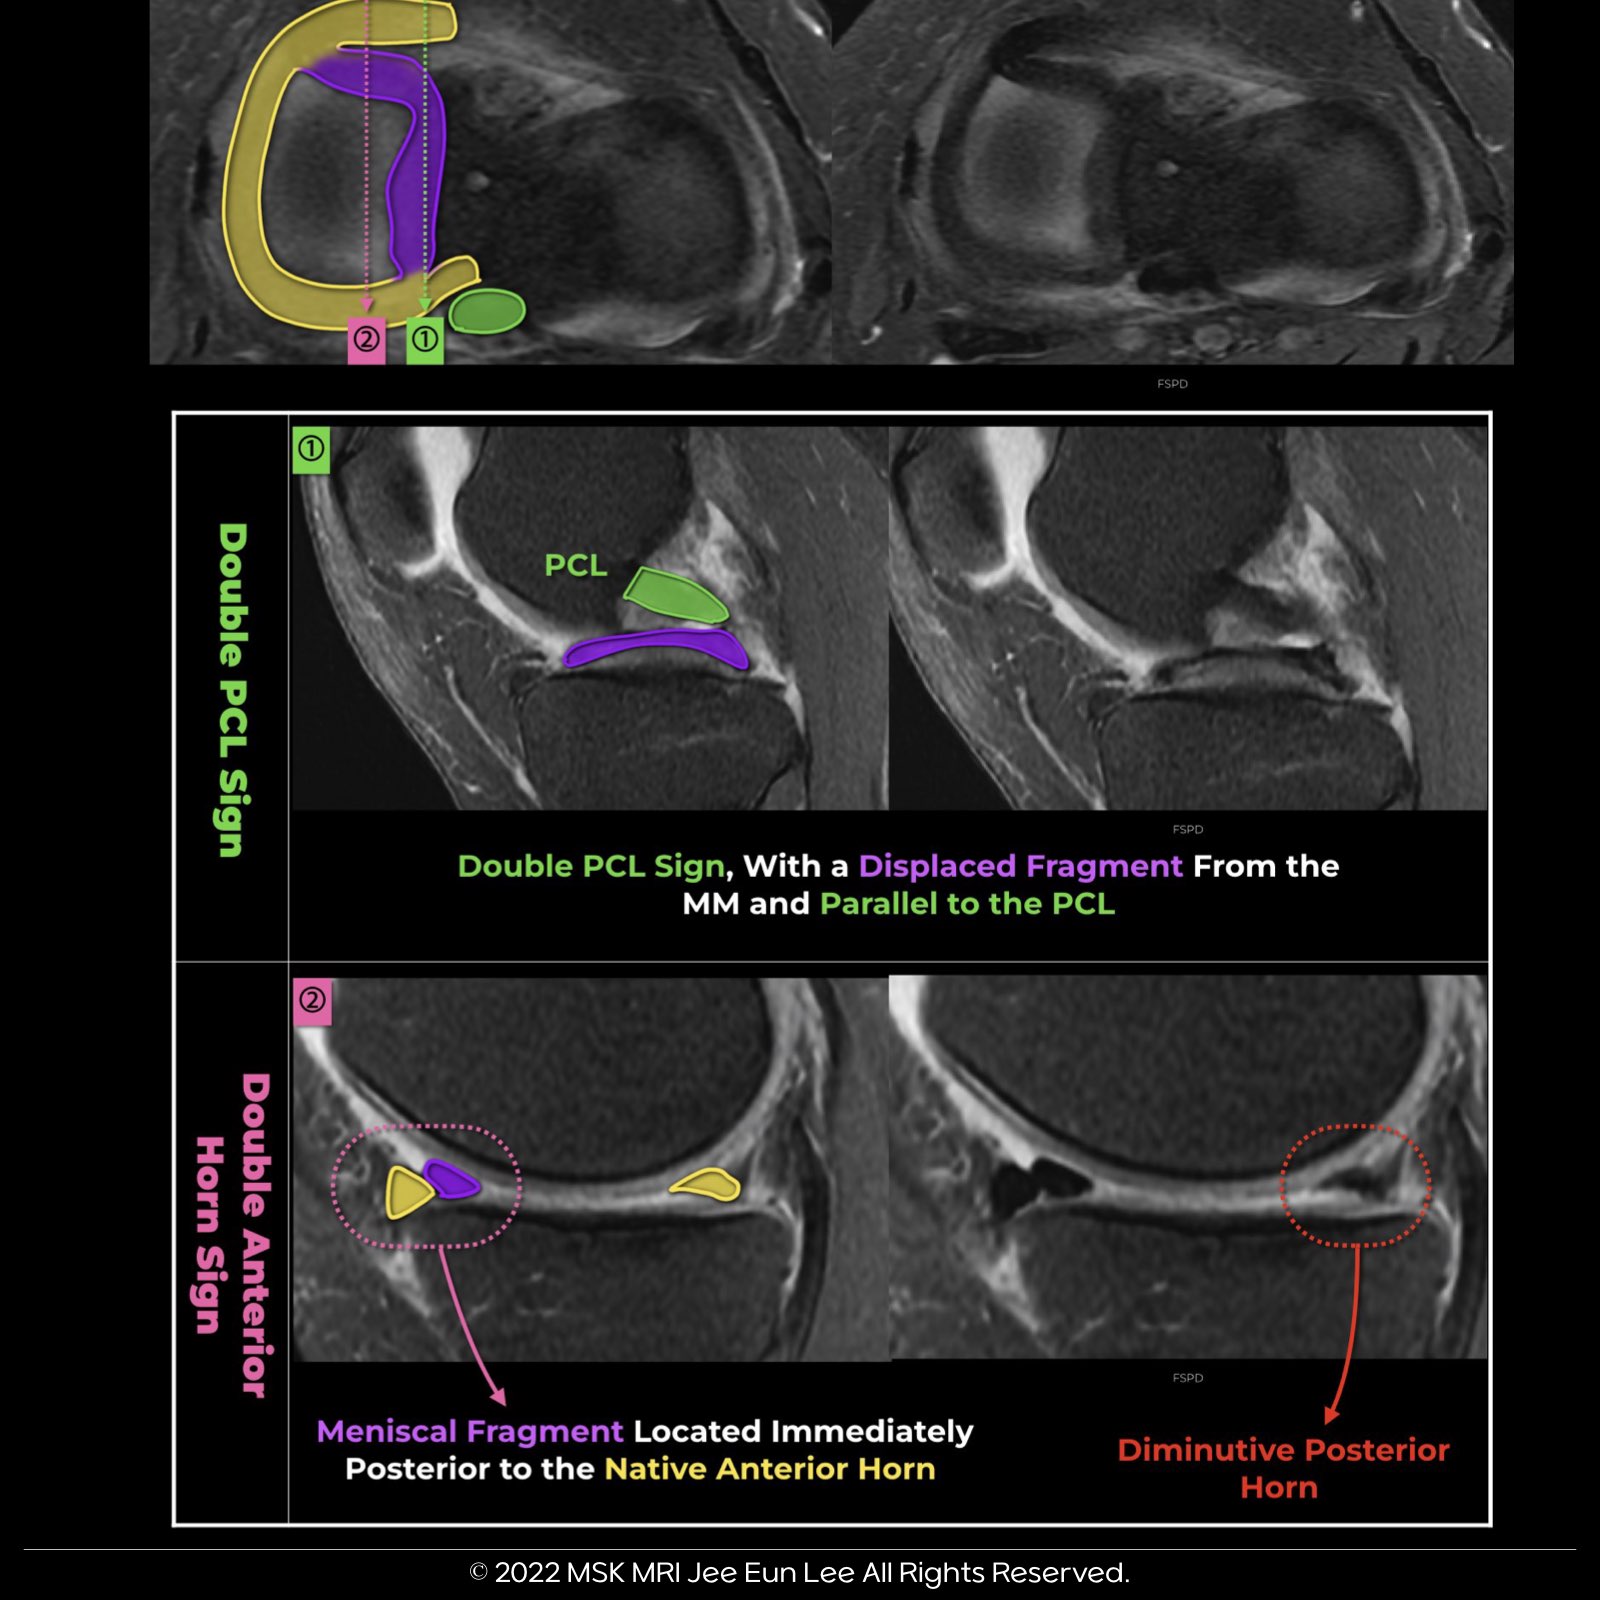

๐งฉ Double Anterior Horn Sign:

The double anterior horn sign is presented as two adjacent triangular seemingly anterior horns on a sagittal image.

The anterior triangle represents the normal anterior horn, while the posterior triangle represents the displaced bucket handle segment.